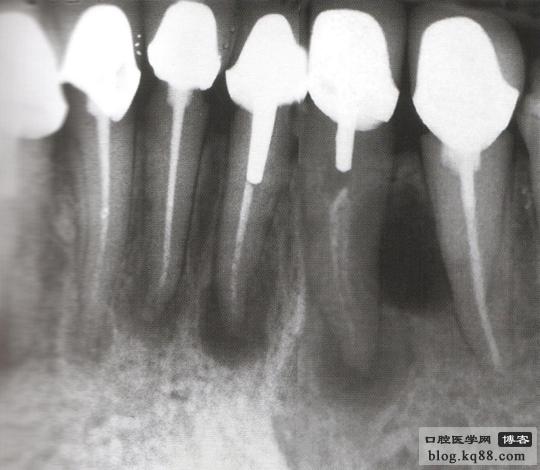

病例2 修復(fù)后根尖出現(xiàn)炎癥冠上開孔再治療

修復(fù)后出現(xiàn)根尖周炎 去除原根充物后試主尖

熱牙膠充填后 一年后復(fù)查病變愈合